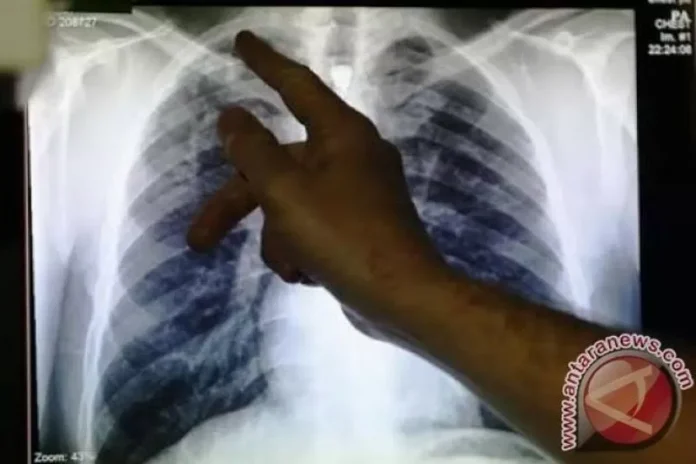

Sekitar 141 tahun yang lalu–24 Maret 1882– seorang ilmuwan Jerman Robert Koch pertama kali menyampaikan temuannya tentang bakteri penyebab TBC, yang dapat menyerang bagian tubuh mana pun, seperti ginjal, tulang belakang, dan otak.

Dia menjelaskan bahwa satu-satunya vaksin yang dikembangkan untuk melawan TBC, vaksin BCG, telah berusia lebih dari 100 tahun dan tidak cukup melindungi remaja dan orang dewasa, yang bertanggung jawab atas sebagian besar penularan penyakit.

Kepada Bergelora.com di Jakarta dilaporkan terpisah, dokter spesialis anak RSCM Jakarta Pusat, Dr. dr. Nastiti Kaswandani, Sp.A (K) mengungkapkan, tuberkulosis (TBC) bukanlah penyakit keturunan, melainkan penyakit menular.

Dani mengungkapkan, anak paling sering tertular TBC dari kontak erat dengan orang terdekatnya. TBC paling sering ditularkan dari orang dewasa melalui percikan ludah, batuk, atau bersin yang sudah mengandung kuman TBC.

Gejala-gejala TBC yang sering ditemui pada anak diantaranya, demam berkepanjangan selama dua pekan, berat badan sulit naik bahkan malah turun selama dua bulan berturut-turut, dan malaise (lesu, lelah, lemas, letih, lemah) atau kondisi dimana anak terlihat pasif dan tidak bergairah saat melakukan aktivitas.